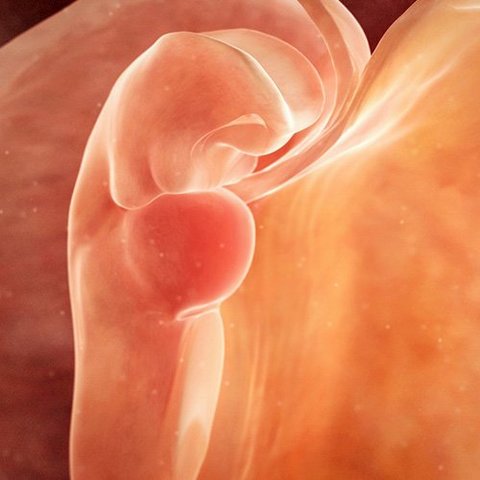

Semana 2

Se desarrolla lo que denominamos embrión, que tiene, básicamente, una cabeza, un tronco y una cola rizada.

Esta semana de embarazo está marcada por:

- La sujeción del blastocisto en el útero, ya que va a ser su “casa” durante todo el embarazo.

- La creación del saco o cavidad amniótica incluido el líquido amniótico..

- La cavidad coriónica, donde estará fijado el embrión sobre un pedículo de fijación, que se transformará en el cordón umbilical.